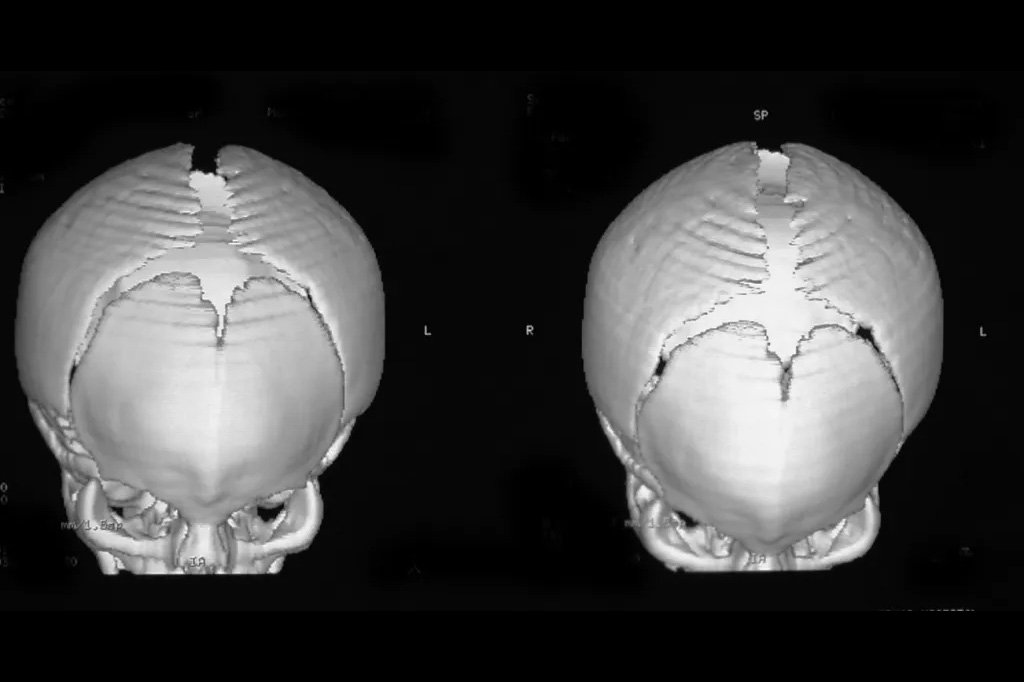

At El Paso Craniofacial Team, the primary treatment for craniosynostosis is surgery. First performed in the late 1800s, surgical approaches have continued to evolve and improve. The two main approaches are Calvarial Vault Remodel (CVR) and endoscopic-assisted surgery, with each tailored to the child’s age, the affected suture, and the severity of the condition.